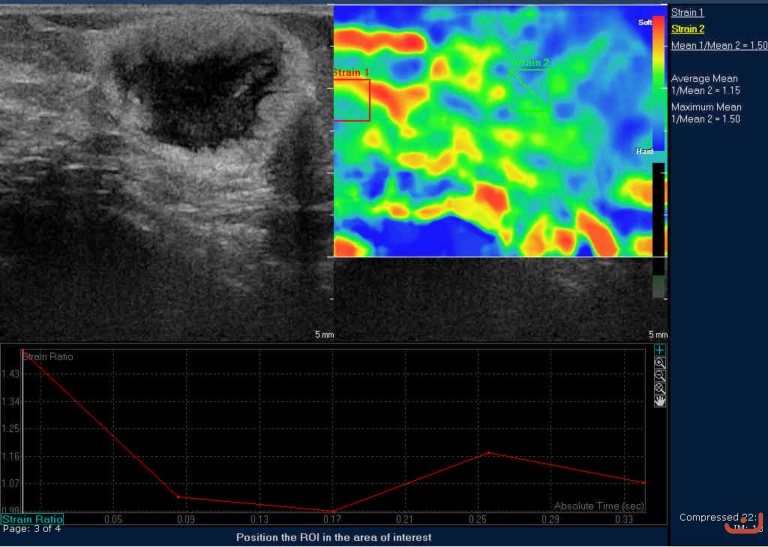

Case 41-E1

Malignant solid mass